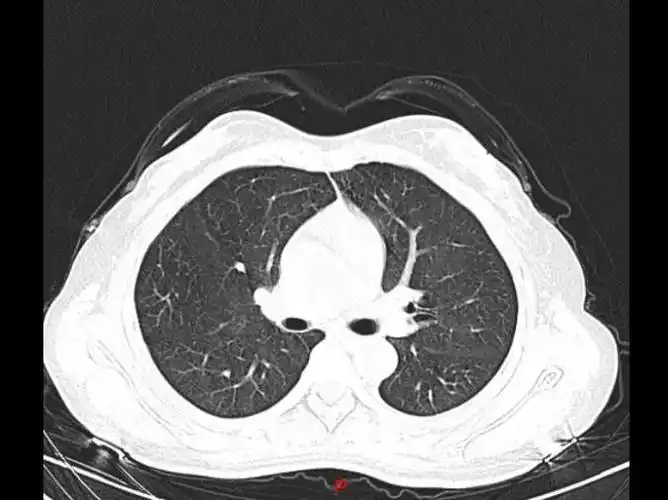

原创做肺部ct可以查出什么病提醒检查前注意这5项

这是一张胸部ct,是什么问题?